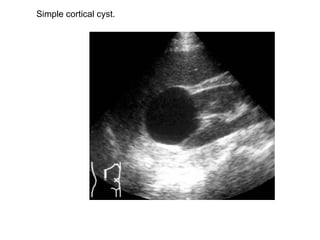

Simple cortical cyst.